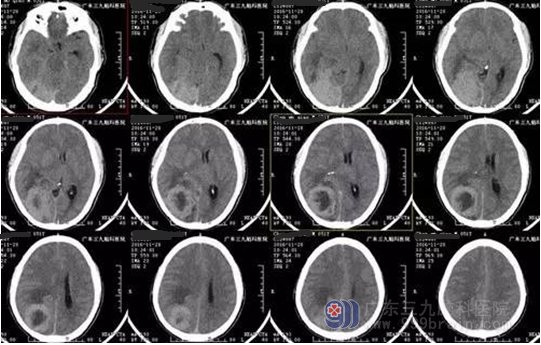

陈男子,51岁,头痛伴视物模糊2月余入院,CT提示右侧顶枕部类圆形占位,其内可见低密度影,占位效应明显,周围见低密度水肿带,MR见病变增强后明显强化,囊变区不均匀强化呈放射状分隔,病灶范围约52mm*46.8mm*64.4mm,诊断:右顶枕叶巨大脑膜瘤。

▲术前CT

本例患者术前为头晕伴视物模糊,视物模糊与病变位于枕部损伤视觉皮质有关。MR提示呈长T1稍长T2为主异常信号, 其内示囊变区明显长T1长T2异常信号,病变中心囊变低信号,病变及其周围多发细小流空血管,增强后明显强化,囊变区不均匀强化呈放射状分隔,病灶范围约52mm*46.8mm*64.4mm。CT及MR均可见低密度及低信号囊变影,类似肿瘤中间“黑洞”。